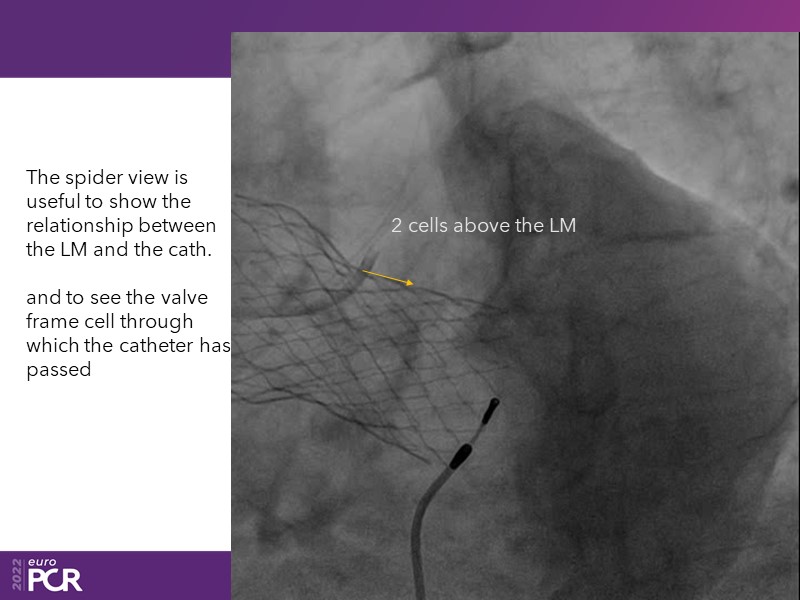

Consult this session to learn how to contribute to streamlined pre- and post-TAVI patient pathways, to discover updates on the optimised TAVI procedure and appreciate the variances in different valve designs and the long-term patient outcomes, as well as to discuss the right time of PCI in TAVI patients (steps on the procedure).